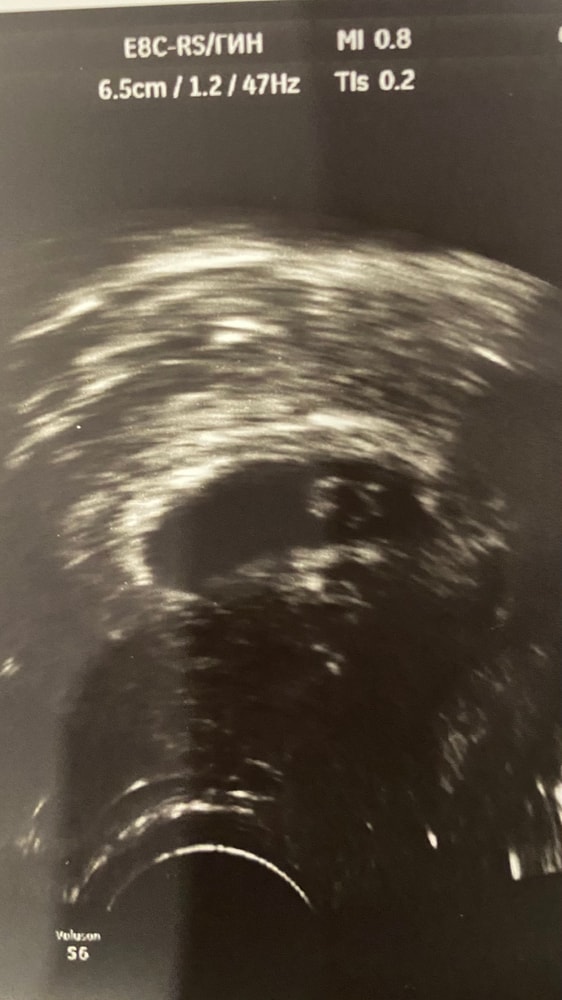

31 дпп УЗИ нашли эмбрион СБ+

Результаты УЗИСегодня состоялось второе узи:

плодное яйцо 24 мм

хорион кольцевидный

желточный мешок 3,4 мм

эмбрион визуализируется, ктр 8 мм 🦐

СБ +, ритм правильный. Ухом пока не слышно

Заключение: маточная беременность 6-7 нед, прогрессирующая 🙏